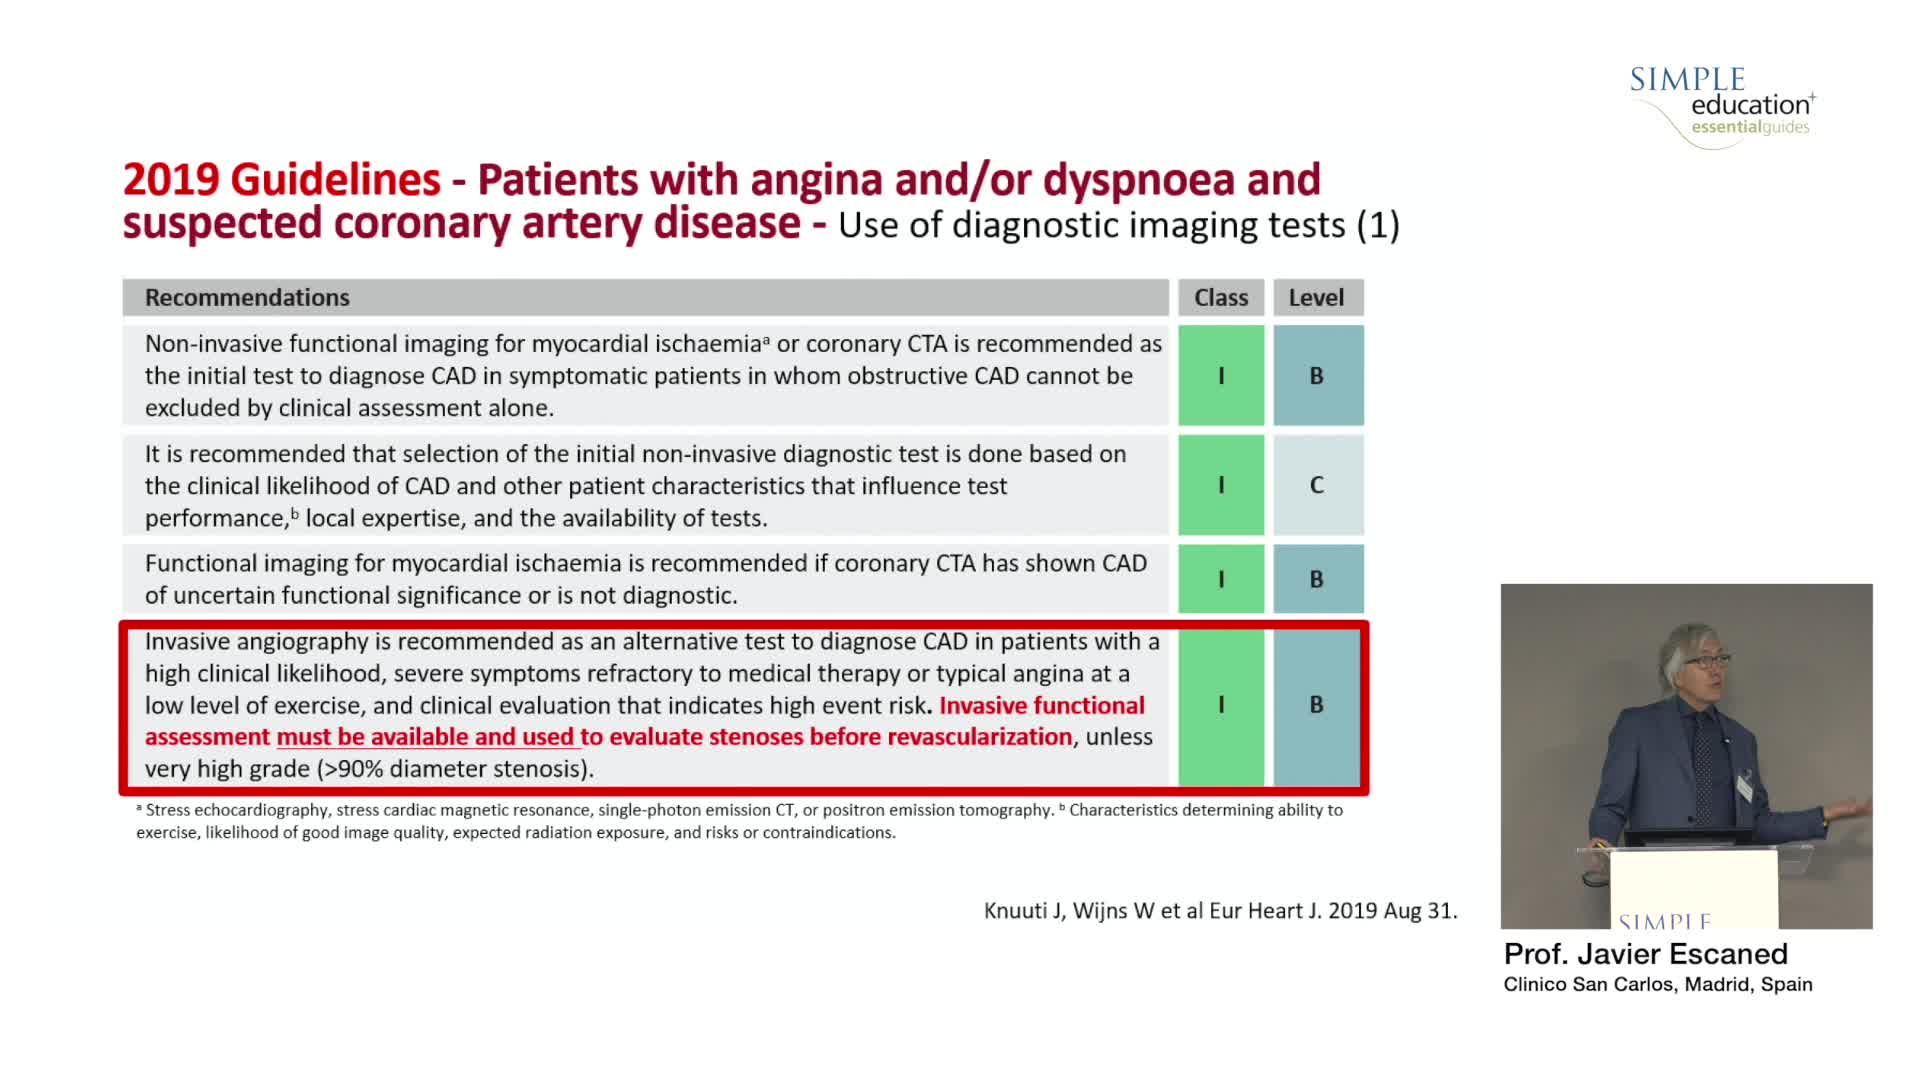

Best practices and personalised medicine in complex PCI - Prof Javier Escaned

Revascularisation in stable angina: a contemporary perspective - Dr Rasha Al-Lamee